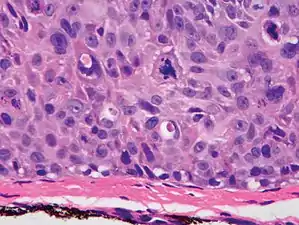

Invasive disease

In invasive cSCC, tumor cells infiltrate through the basement membrane. The infiltrate can be somewhat difficult to detect in the early stages of invasion: however, additional indicators such as full thickness epidermal atypia and the involvement of hair follicles can be used to facilitate the diagnosis. Later stages of invasion are characterized by the formation of nests of atypical tumor cells in the dermis, often with a corresponding inflammatory infiltrate.[12]

- High magnification demonstrates the pleomorphism of the invading keratinocytes[12]